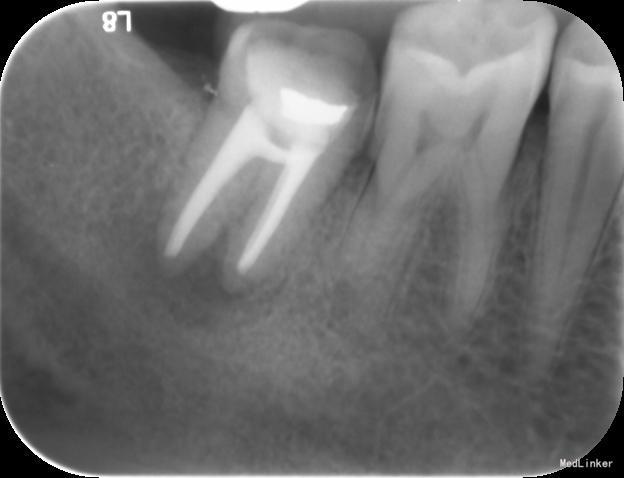

检查:右下7髓腔开放,可见髓腔内食物残渣及部分银汞充填体,叩痛(++), 冷热刺激无反应,松动1度,牙体已制备,牙合龈距离低,X线片示根尖区密度减低区。

诊断:难治性根尖周炎 治疗计划:告知患者病情,治疗难度及预后,拟行根管再治疗,但术后效果不确定,如若不理想拟需行根尖手术甚至牙拔除术。患者知情同意,并要求尽量行保留牙齿治疗。 处置:第一次 揭全髓顶,去腐,疏通根管,测量工作长度,机扩预备至S1,超声荡洗,激光消毒,封CP球。口服抗炎药。一周后复诊。 第二次 复诊无叩痛,暂封物在。去除暂封物,双氧水和盐水交替冲洗,EDTA伴随下根管预备至F2,超声荡洗,激光荡洗+激光消毒,封氢氧化钙。两周后复诊。 第三次 复诊无叩痛,暂封物在。 去除暂封物,双氧水和盐水交替冲洗,EDTA伴随下根管预备至40号,超声荡洗,激光荡洗+激光消毒,封vitapex,玻璃离子体充填。拍X线片。一月后复诊。 第四次 复诊无疼痛 旧充填体在 拍X线片可见根尖阴影变小,故未行任何治疗,嘱患者1月后再次复诊。 第五次 复诊无疼痛 旧充填体在 拍X线片未见根尖阴影变小,故去除旧充填体,冲洗,去除vitpex,根管再次预备,双氧水和盐水交替冲洗,超声荡洗,激光荡洗+激光消毒,封氢氧化钙。两周后复诊。 第六次 复诊无疼痛 去除暂封物,冲洗,见根管内无渗出,试尖,超声荡洗,激光荡洗和消毒,干燥,AHplus糊剂和热牙胶充填,糊剂超填,玻璃离子体充填。请口腔外科医生会诊是否可行根尖手术,外科医生建议因手术难度大,且病变与下颌神经管接近,建议随诊观察,暂不考虑行根尖手术。必要时考虑意向性牙再植术或者牙拔除术。嘱患者1月后复诊,结果患者失诊。